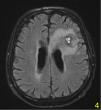

A stereotactic biopsy was made for histological diagnosis. Immunohistochemistry analysis demonstrated that CD20, CD5, and Cyclin-D1 were positive (Figure 2). The patient was re-evaluated with the diagnosis of MCL from the brain parenchymal tissue. PET-CT showed no other involvement rather than the brain parenchyma (Figure 3). The patient, who was diagnosed with isolated CNS MCL, was given MATRix (methotrexate, cytarabine, thiotepa, rituximab) combination chemotherapy, especially known for its efficacy in MCL and CNS lymphoma. On the 8th day of the regimen, the mass was reduced in the cranial MRI (40×34×20 mm) (Figure 4). On the 25th day of the regimen, his alertness increased, he started to communicate in the form of single words. His nutrition and movements improved. The MRI repeated on the 30th and 45th day, the mass was regressed even further (36×25×17mm and 23×22.5×15mm respectively) (Figure 5a,b, Figure 6a,b,c).